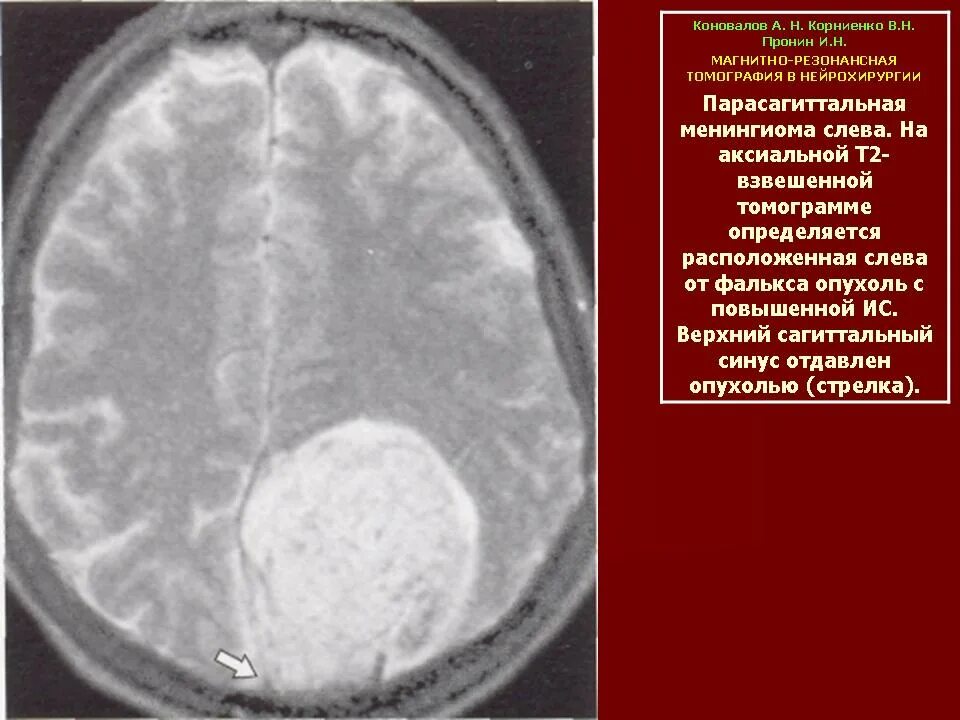

Менингиомы головного мозга мкб